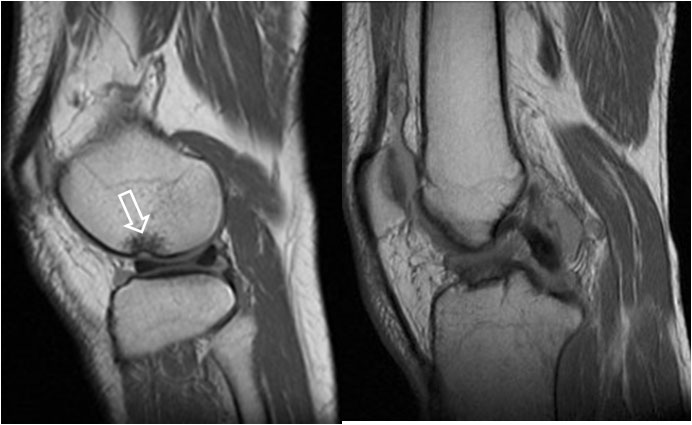

SIGNO DEL DOBLE LIGAMENTO CRUZADO POSTERIOR

Signo de rotura meniscal en los cortes sagitales de Resonancia magnética. El fragmento roto (flecha blanca) se desplaza medialmente y se coloca bajo el ligamento cruzado posterior (flecha roja), dando la imagen de duplicación de éste.